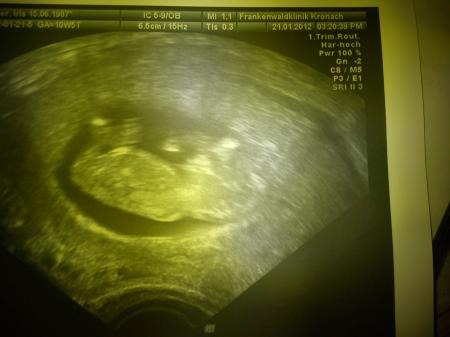

Ich kann es nicht glauben aber aus einen punkt wurde das. Mußten gestern ins Krankenhaus wegen einen treppensturz. War aber alles ok. Sie meinte ich habe ein sehr lebhaftes Kind. Na könnt Ihr es auch sehen mein schatz nahm seine hand und steckte sie in den mund hat die ärztin gleich ein bild von gemacht. Könnten des richtig sehen. :-) Mein Mann war richtig stolz als er das sah jetzt kann er mehr damit anfangen :-) Ab heute 12 Woche :-)

hier das bild

Laut den bild ist es 6,5cm groß. Konnte ja keine fragen stellen da mein Mann die ärztin lieber mit fragen genervt hat :-)